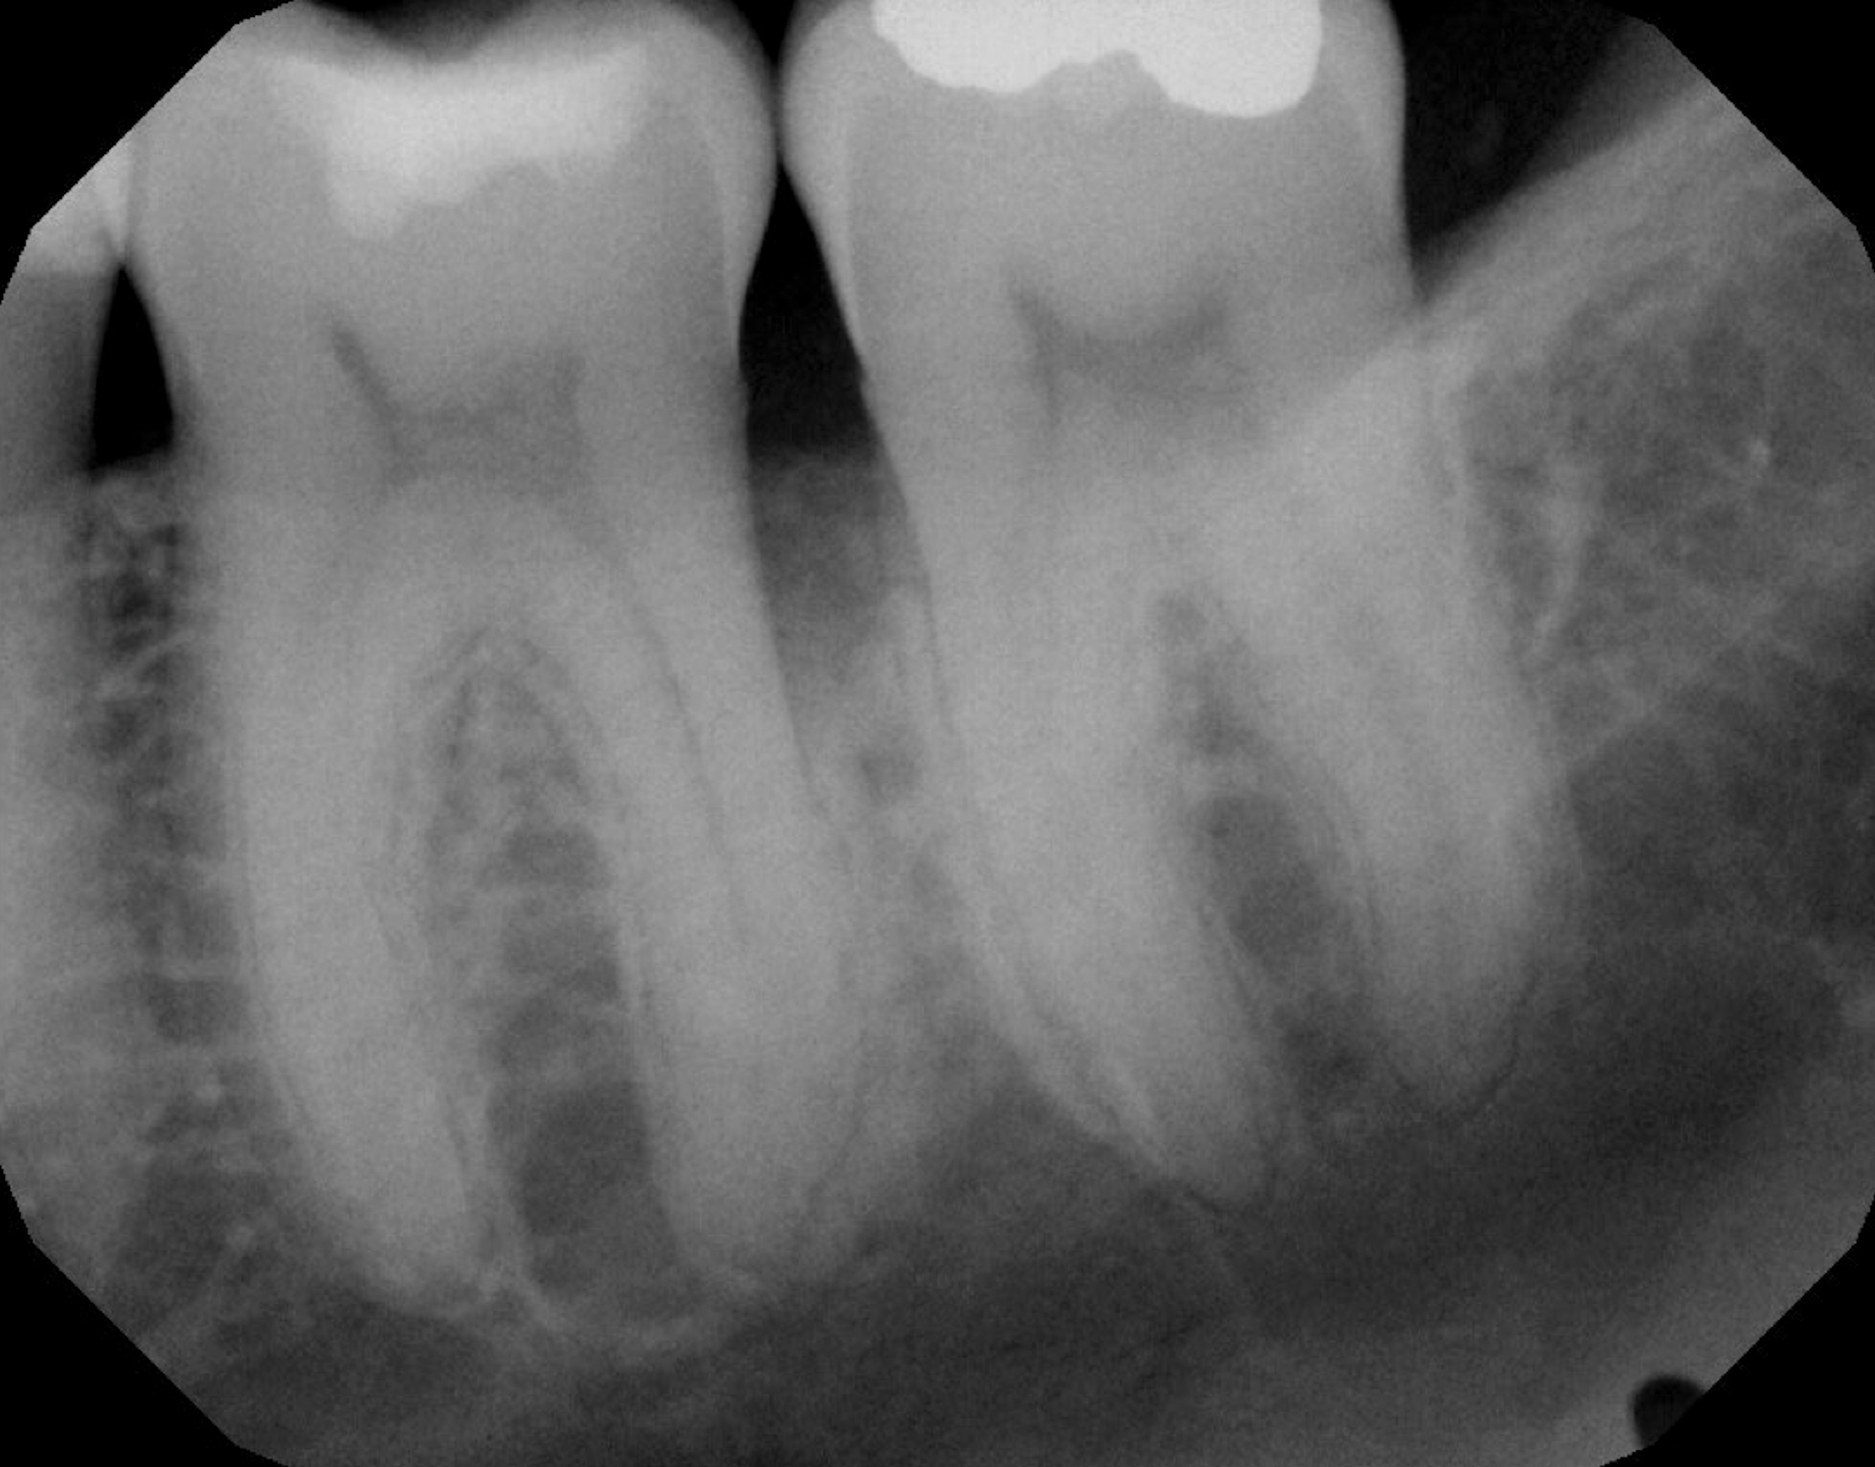

Fig 4. Periapical radiograph revealing a distal intrabony defect at tooth No. 19.

Figure 4

In the case presented, a 56-year-old healthy nonsmoking male patient, diagnosed with periodontitis stage III, localized, grade B, had been under care in a private practice periodontal office (RAL) for 25 years. He had a history of good compliance with his treatment (full-mouth plaque score <20%). During the COVID-19 pandemic, the patient missed three supportive periodontal therapy (SPT) visits over a year, resulting in periodontal breakdown interproximal between teeth Nos. 18 and 19 (mandibular left second and first molars, respectively). At his most recent periodontal maintenance visit, significantly increased periodontal probing depths of up to 10 mm with bleeding on probing were noted (Figure 1 through Figure 3). The periapical radiograph revealed a deep, narrow three-wall intrabony defect at the distal aspect of tooth No. 19, with class I buccal furcation involvement (Figure 4). According to the periodontal risk score (PRS),15 formerly known as the Miller-McEntire periodontal prognosis index, the tooth prognosis at the patient's initial examination was "good" (score = 5), taking into account that he was unaware of his hemoglobin A1C (HbA1c) levels. This scoring motivated the patient to be tested, and his follow-up HbA1c was <6%, thus reducing his PRS to 3, which was considered "excellent," as the PRS target goal for regenerative procedures is a score of <5.15